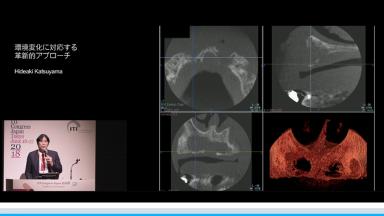

環境変化に対応する革新的アプローチ

インプラント治療において、急速な高齢化や低侵襲治療など患者のニーズの変化、審美へ要求、難症例の増加、デジタルの発展や歯科業界の全体の構造的な変化など激烈な変化が見られる。演者は革新的ななアプローチでどの様に対応するかについて解説する。

- デジタルの発展とその対応を理解できる